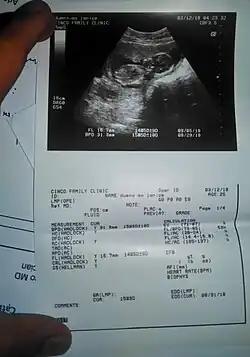

An ultrasound result on fetal biometry printed on a piece of paper -